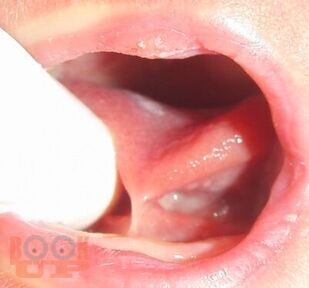

В учебном пособии представлены особенности организации и проведения в женских консультациях, в рамках школы будущих родителей, занятий по профилактике основных стоматологических заболеваний у детей первых лет жизни.

Пособие предназначено для последипломного обучения организаторов здравоохранения, врачей-стоматологов и гигиенистов стоматологических, а также для акушеров-гинекологов и психологов, работающих в женских консультациях.